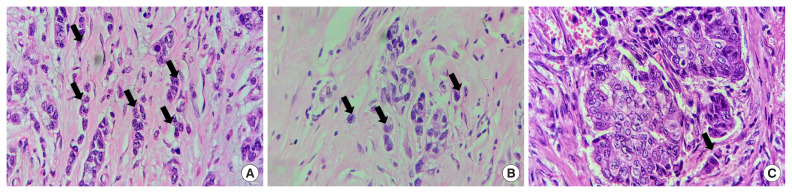

Purpose: Breast cancer is one of the most common cancers globally, with an increasing incidence rate. It is a heterogeneous disease, and early metastasis remains a challenge. Tumor budding, defined as single tumor cells or small clusters at the invasive front, has been suggested as a prognostic marker in various cancers, including breast cancer. This study aims to evaluate tumor budding in invasive breast carcinoma using the International Tumor Budding Consensus Conference (ITBCC) scoring system and explore its association with pathological characteristics and prognosis.

Methods: A retrospective study was conducted on 100 mastectomy specimens of histopathologically confirmed invasive breast carcinoma, excluding cases that underwent chemotherapy or radiotherapy. Tumor budding was classified as low, intermediate, or high based on the ITBCC scoring method, and associations with clinicopathological features were analyzed using appropriate statistical tests.

Results: Tumor budding was classified as high in 52% of cases. A significant association was found between high tumor budding and higher tumor grade (P<0.001), negative estrogen receptor and progesterone receptor status (P<0.001), positive HER2neu status (P=0.003), and high Ki-67 levels (P<0.001). High tumor budding was also linked to higher T stage, and dermal lymphovascular invasion (P=0.001). Our findings support previous studies showing that high tumor budding is associated with poor prognostic factors such as higher tumor grade, negative hormone receptor status, and higher T stage.

Conclusion: Tumor budding is a potential prognostic marker in breast cancer, associated with more aggressive tumor characteristics.